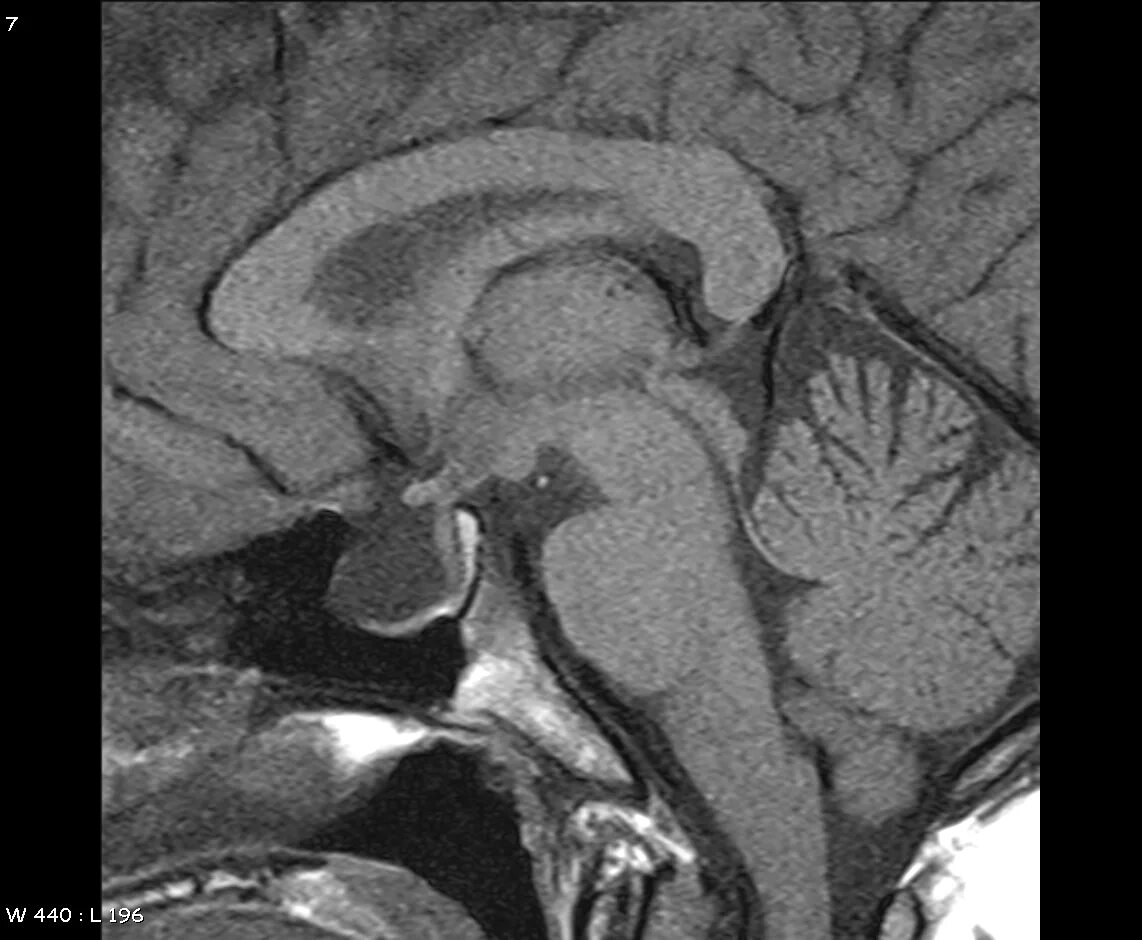

Формирование пустого турецкого седла в головном мозге